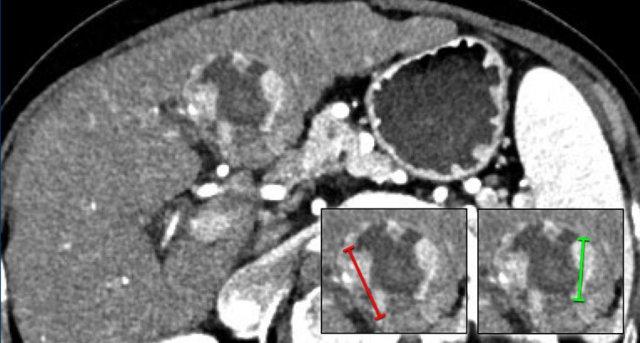

LRTR còn khả năng sống

Khi đo khối u còn khả năng sống, chỉ đo vùng ngấm thuốc hoặc thải thuốc liên tục lớn nhất (không đi qua vùng không ngấm thuốc).

Nếu vùng ngấm thuốc còn sót lại trong tổn thương có dạng nốt, cần ghi nhận nốt lớn nhất.

Nếu một khối u mới xuất hiện tiếp giáp với tổn thương đã điều trị, tổn thương này cần được phân loại theo hệ thống LI-RADS dành cho tổn thương chưa điều trị.

Nếu một tổn thương mới được ghi nhận tại bờ phẫu thuật, tổn thương đó cần được phân loại theo thuật toán dành cho tổn thương đã điều trị.